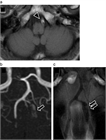

1. 急性期の血管内治療について、解離による頭蓋外頸動脈狭窄とそこからの塞栓による頭蓋内動脈閉塞については血栓回収療法の有用性が示されてきている。

1. MRA、CTAによって解離の特徴的な所見を見逃さないようにする。